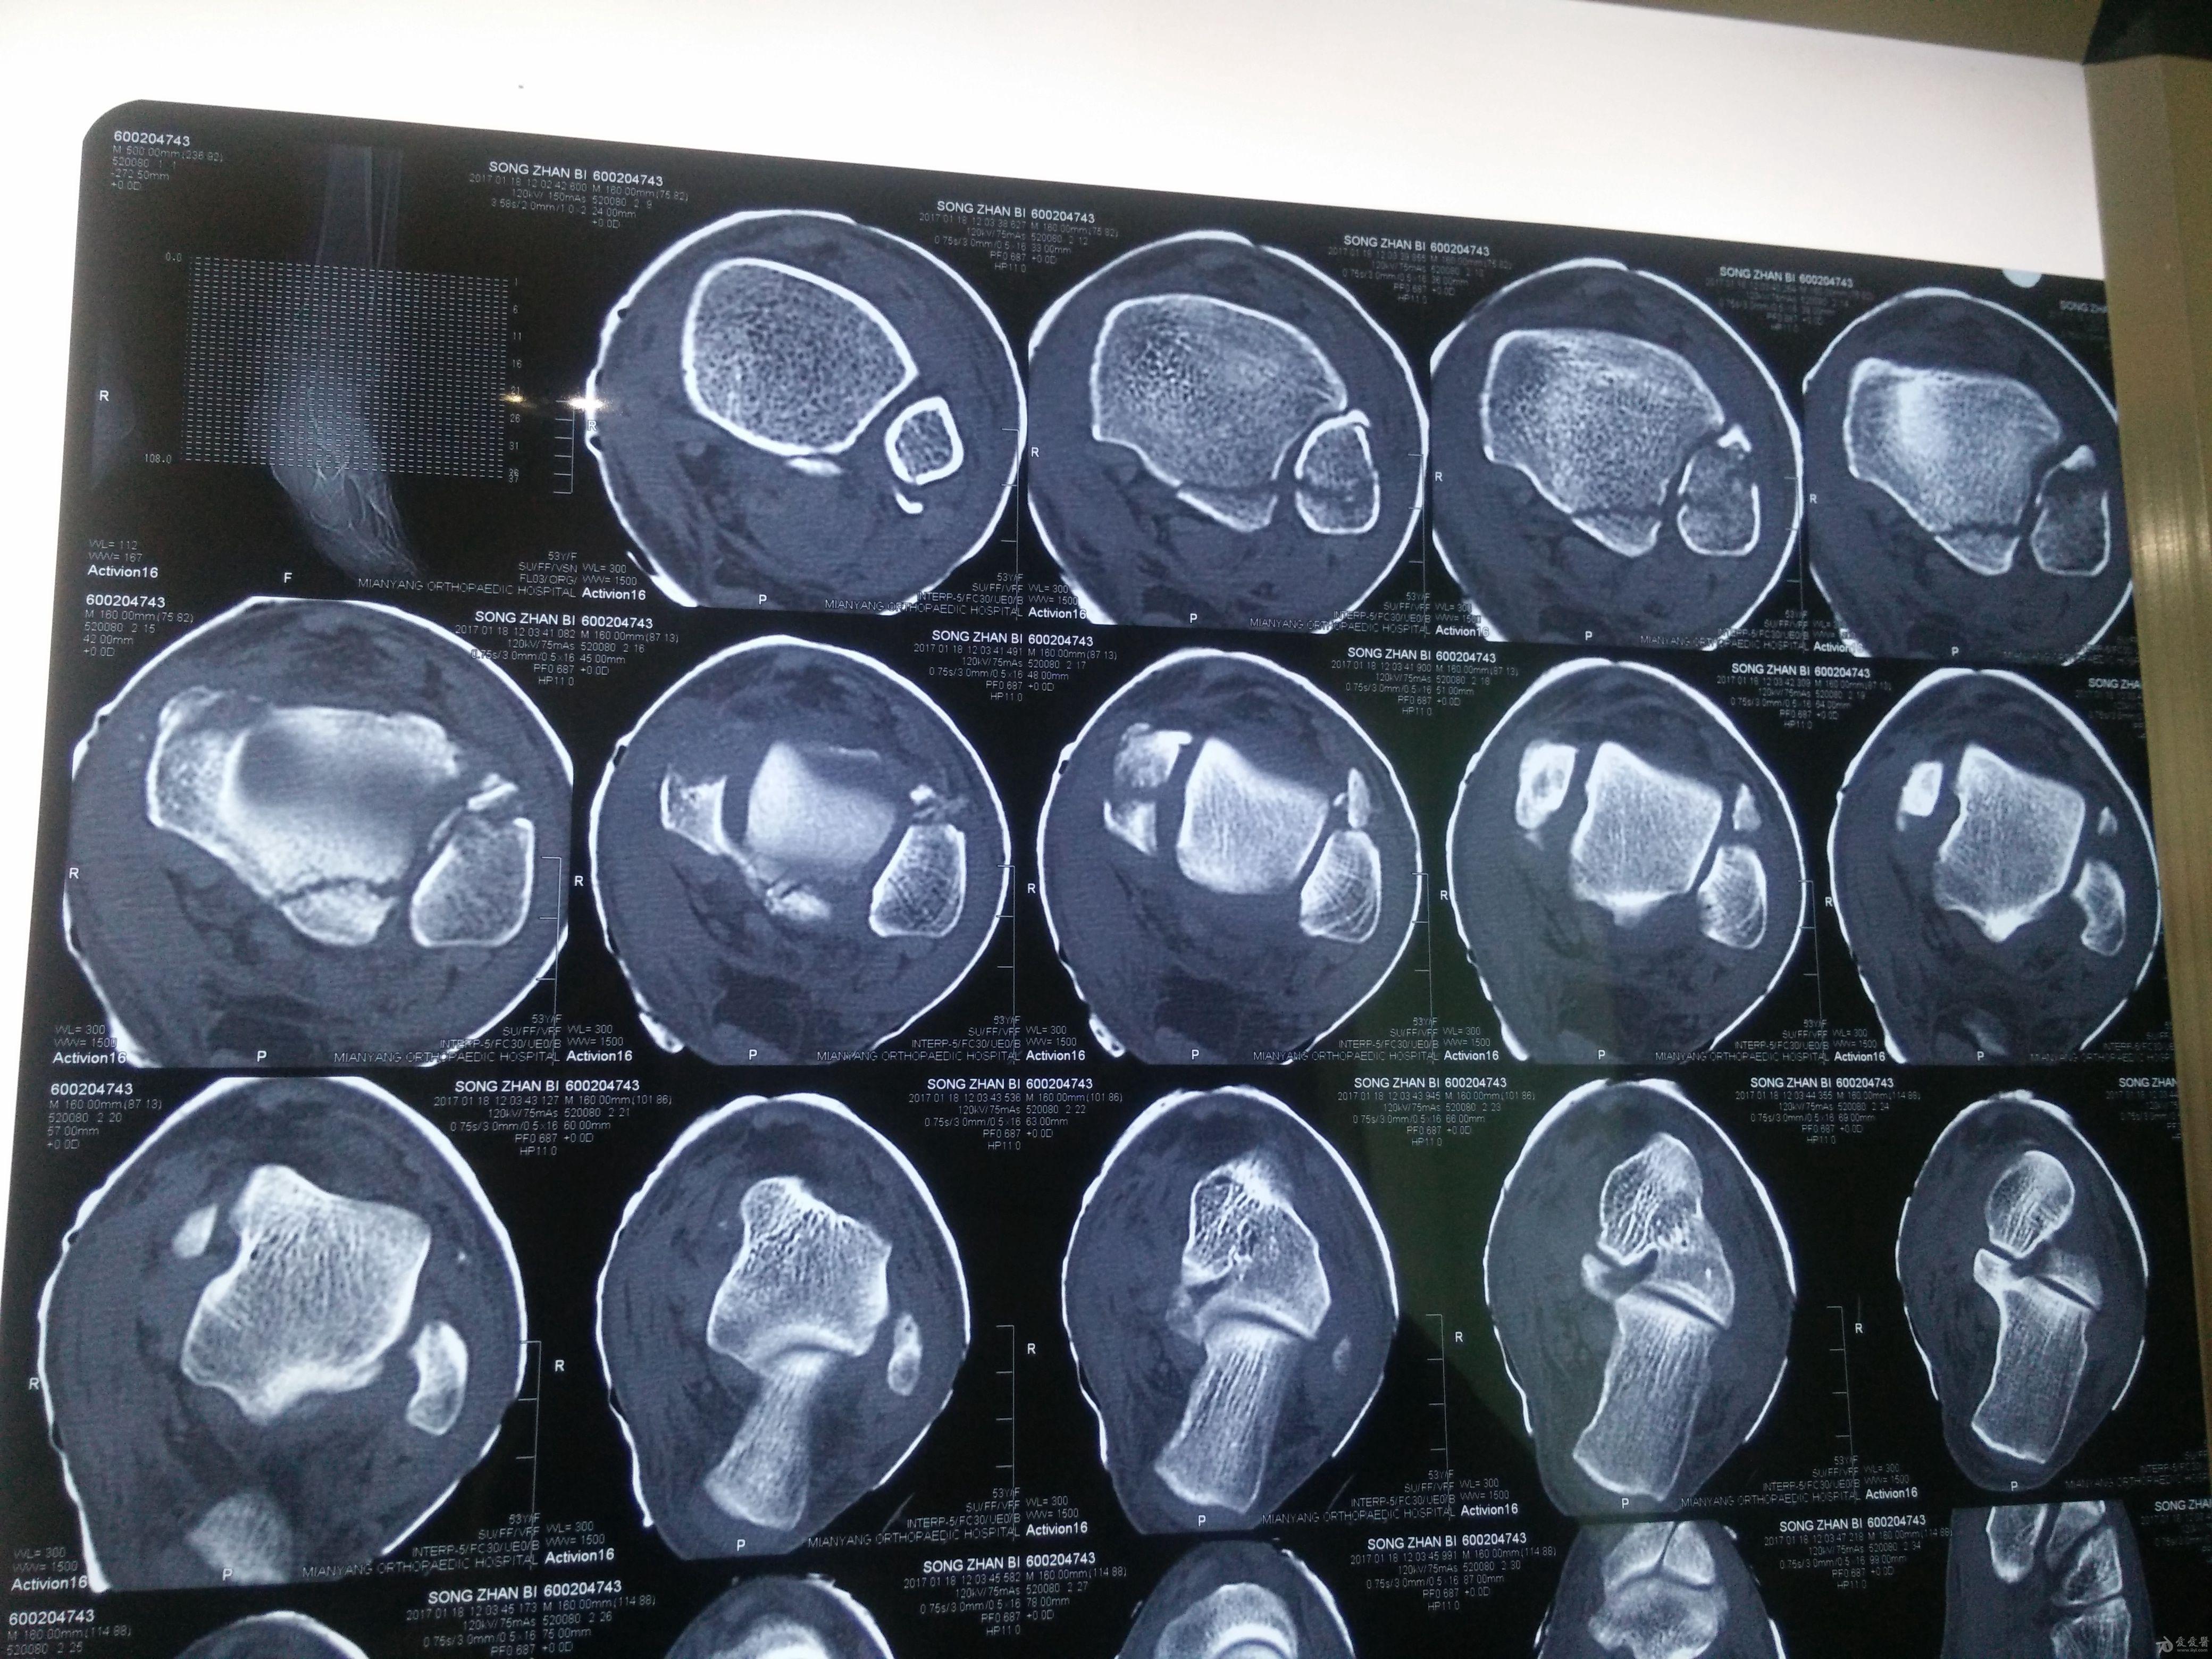

左三踝骨折手术治疗

患者女,外伤后左踝关节活动受限1小时入院,

入院后查体:左踝关节肿胀,活动受限,行DR及左踝关节CT检查,如下图,手术待肿胀消退后行手术治疗,目前愈合良好,请问问各位老师,好久可以下地呀, 下胫腓联合镙钉3个月取呀,